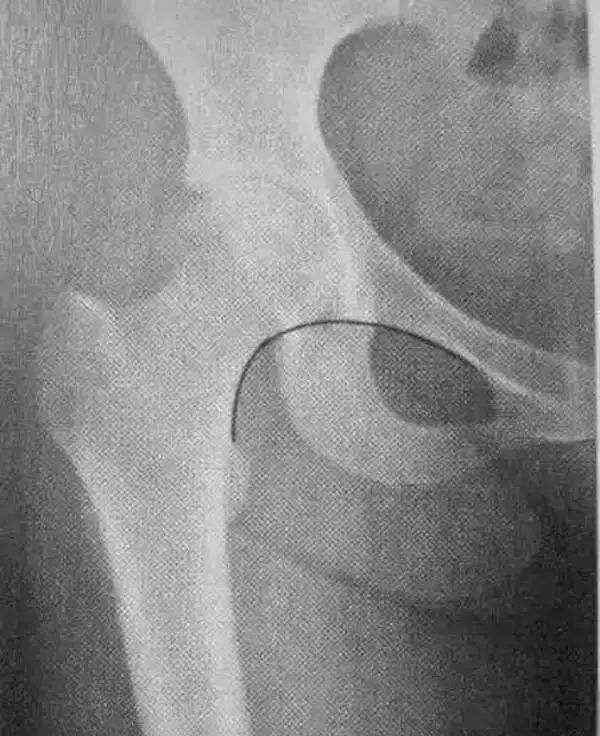

骨科精读髋关节的x线解剖及应用技巧最全总结

股骨x线解剖

股骨正侧位x线图片